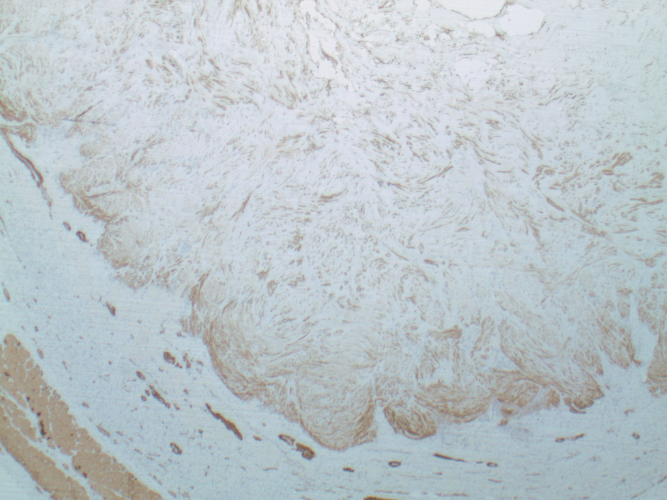

The patient elected to have the mass removed after a full, detailed discussion of conservative and surgical options. Surgically, we made a curvilinear incision along resting skin tension lines, exposing the plantar fat pad. Blunt and sharp dissection deepened the incision to the plantar aspect of the flexor hallucis longus tendon, and allowed visualization of the mass. Once fully exposed, we excised the tumor, which was consistent with the MRI report. It was encapsulated, measured 3.3 x 1.8 x 1.0 cm, and presented with central hyaline degeneration and infarction. After irrigation, we performed the remaining soft tissue closure in layers, with a small drain placed to prevent possible hematoma formation. The postoperative course involved four-to-six weeks of guarded weight-bearing in surgical shoe, with limitations on driving.